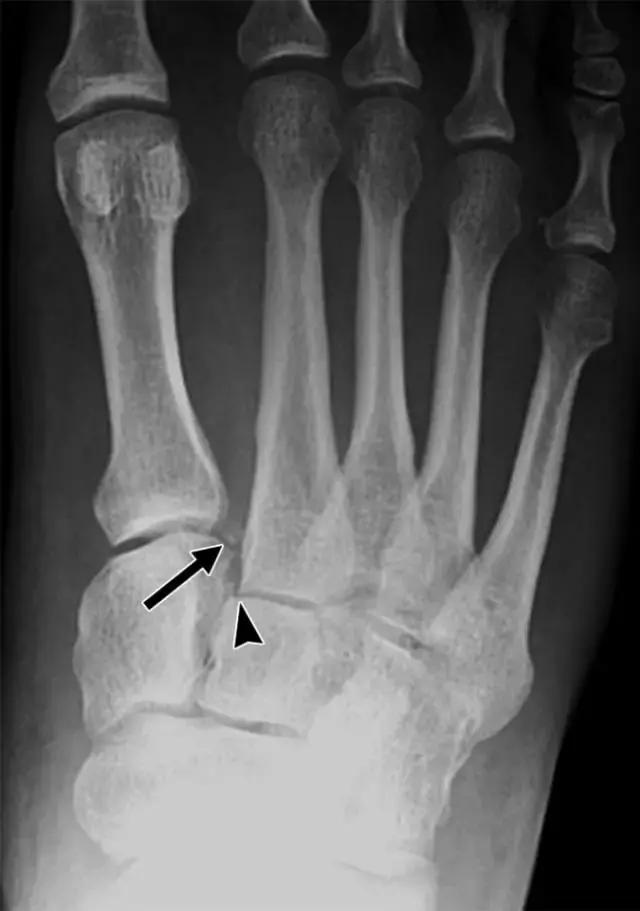

跖跗关节复合体由五个跖骨关节组成。跖跗关节的骨结构由多个韧带支撑。跖跗损伤最常见的机制是通过关节的轴向载荷,而脚是刚性跖屈。这种力量向背面驱动跖骨,并产生韧带断裂并沿着跖骨关节骨折。所有跖跗关节损伤的大约20%出现漏诊,误诊往往导致衰弱足不稳定和变性[11]。正常情况下,第一跖骨和楔骨的内侧缘在脚的正位X线片上是对齐的,第二跖骨和中间楔骨的内侧边缘也是一致的。第二跖骨相对于第二楔形关节的横向移位的第一和第二跖骨关节之间的间隙的扩大是最可靠的标志[3],并且在该位置间隙大于2mm表示跖跗韧带伤害和不稳定。然而,不负重的X射线照片可能正常,在这些情况下,承重视图通常是有帮助的(图1A)。

图1A -49岁的女士与跖跗受伤。A,负重前后X线片显示近端第一和第二跖骨之间的间隔扩大。第二跖骨关节(箭头)和第一跖骨关节的内侧偏移以及相关的斑点骨折(箭头)的明显异常。